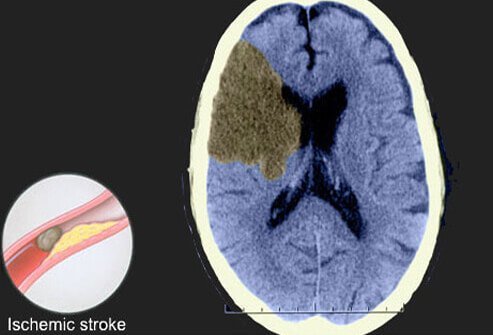

Ischemic Stroke

This slide shows a CT scan of an ischemic stroke, which is responsible for about 80% to 90% of all strokes. Ischemic strokes are caused by clots that reduce or stop blood flow to the brain. The clot may develop elsewhere in the body and circulate to become lodged in a blood vessel in the brain, or the clot may originate in the brain.

Ischemic strokes are usually divided into two main subtypes: thrombotic and embolic.